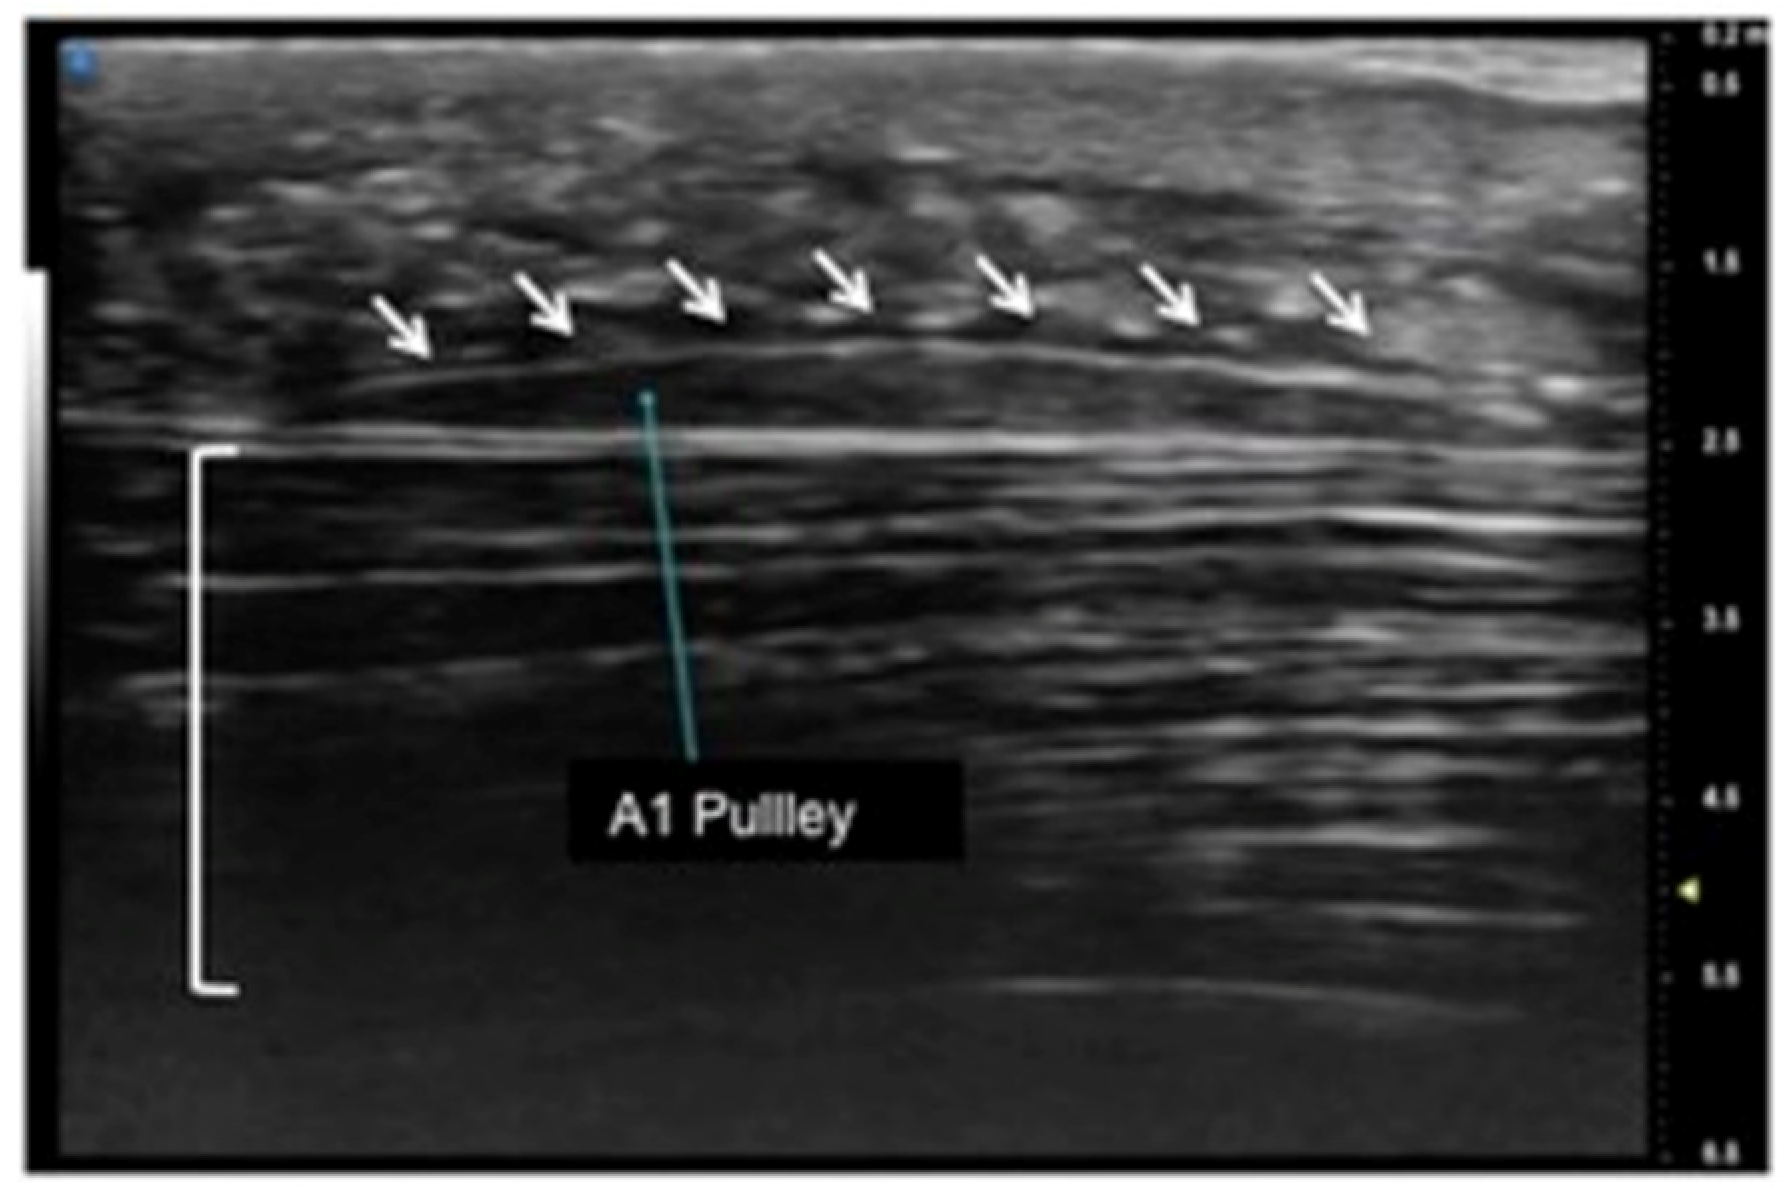

UHFUS encompasses wide applications, especially in the evaluation of hand anatomy and pathological disorders of the upper arm, including the study of pulleys, fascia, retinacula, and other superficial structures of the soft tissues (Figure 1, Figure 2 and Figure 3). Particularly concerning the flexor tendon pulleys, the added value of UHFUS becomes crucial due to the subtle thickness of these structures, with a potential role in the identification of traumatic injuries [24,25,26]. UHFUS can identify pulley ruptures, especially with the dynamic assessment of the tendon-to-bone distance in flexion against resistance. In the evaluation prior to hand surgery, the analysis of hand anatomy can become essential for preoperative planning, postoperative management, and follow-up [27]. Tenosynovitis is defined as hypoechoic or anechoic thickened tissue with or without fluid within the tendon sheath with possible signs of Doppler signals, which are seen in two perpendicular planes [14]. Both tendon disease and tenosynovitis are important features of rheumatoid arthritis (RA), and US represents an ideal tool for their investigation. Tenosynovitis is seen as a combination of synovial thickening within the tendon sheath and tendon sheath effusion [28,29,30,31,32,33,34,35,36].

Figure 1.

Sagittal view of A1 pulley (white arrows) presenting as a fusiform structure with a hypo-echoic signal contoured by a thin hyperechoic line. The superficial flexor tendon is visible (square parenthesis).